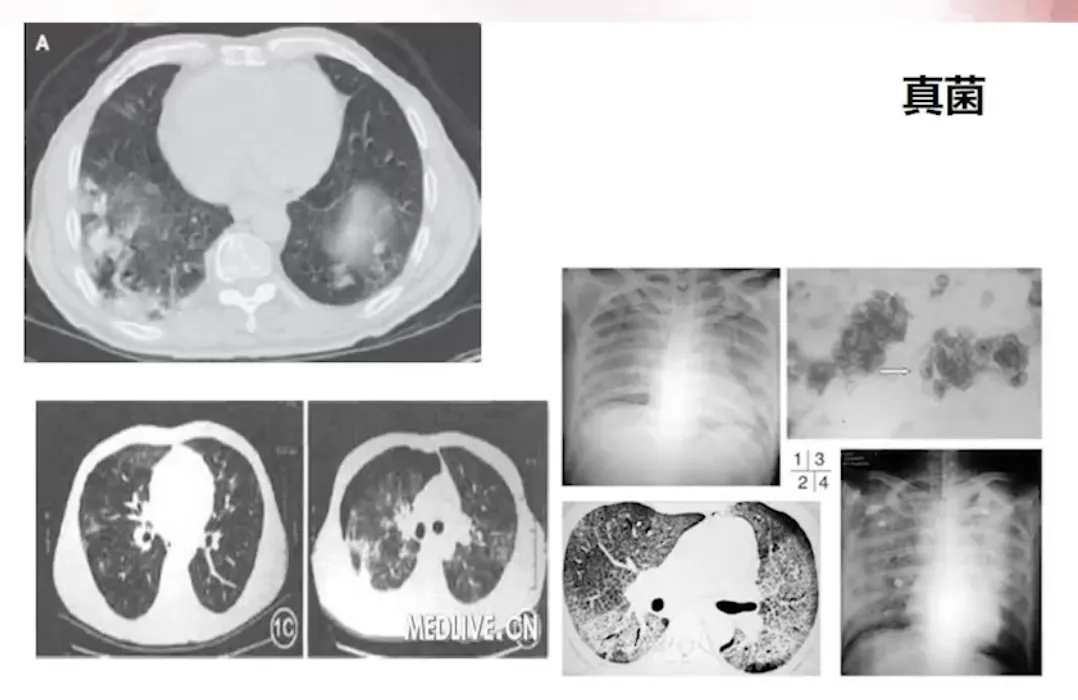

脓毒症的处理